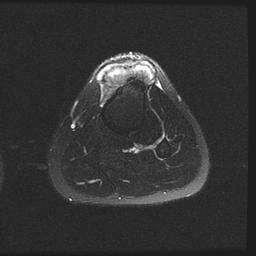

MRI

Parosteal osteosarcoma posterior tibia